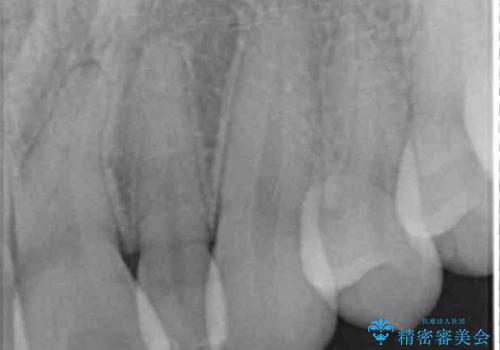

- 左上の前歯が生まれつき小さく、前に飛び出していました。

矯正治療で引っ込めてから、形を左右対称に整えるセラミック治療を行いました。